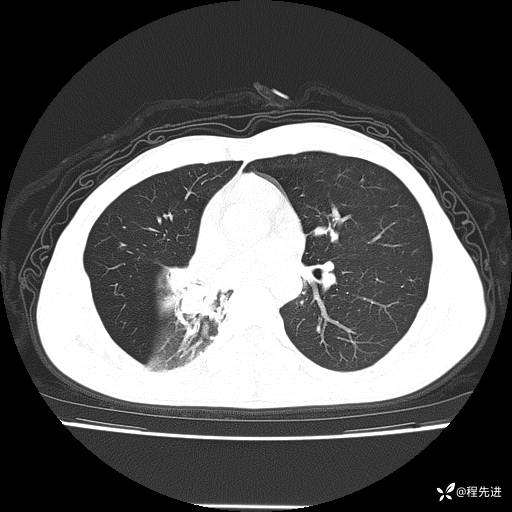

患者性别:男

患者年龄:49岁

主诉:咳嗽、胸痛1周

简要病史:1周前受凉感冒后开始出现咳嗽症状,阵发性连声咳,痰多,黄白痰,不易咳出,伴胸痛、气紧、胸闷,右侧为主,活动用力、呼吸时胸痛明显,曾在当地诊所贴敷膏药仍疼痛

体格检查:T:36.3 ℃ P:80 次/分 R:20 次/分 BP:120/88 mmHg,指脉氧饱和度97%,意识清晰,呼吸平稳,右侧第二、三肋骨压痛,可见膏药贴敷,皮肤无异常,双肺呼吸音粗,未闻及干湿性啰音。心率80次/分,节律整齐,无杂音。腹平软,全腹无压痛无反跳痛

临床诊断:社区获得性肺炎

CT平扫: